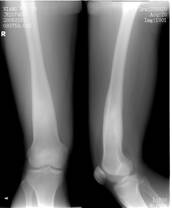

照片名称:右胫腓骨骨折